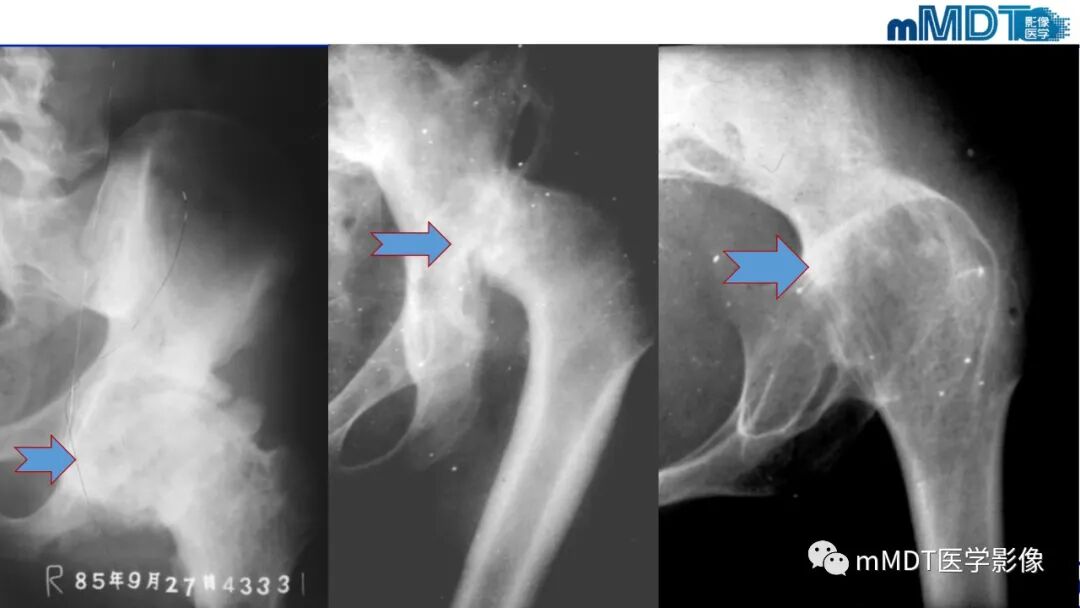

1.平片、CT:活动期表现骨质疏松,股骨头和转子间弥漫性骨密度减低,股骨头软骨下骨皮质吸收,髋臼受累程度轻,无骨侵蚀或破坏,关节间隙保持正常。